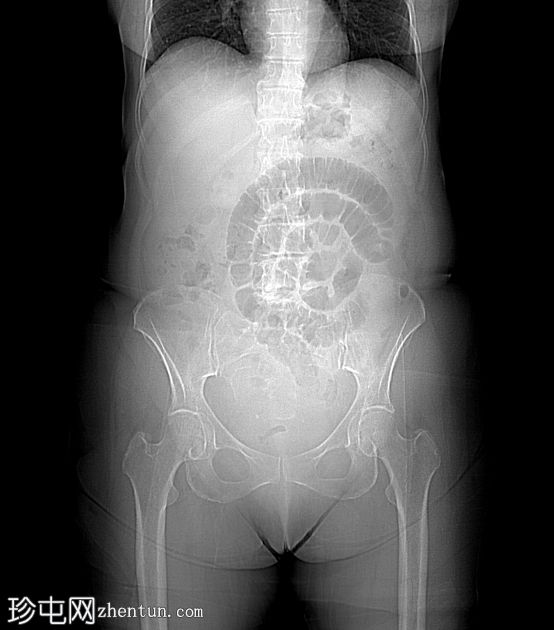

定位扫描

回肠末端长段狭窄,管腔狭窄,肠壁增厚/不规则,几乎延伸至回盲瓣。上游小肠节段扩张和粪便样改变,无重度梗阻。少量腹水。子宫切除术史。骶骨因放射治疗而相对脱钙。

病例讨论

典型的慢性放射性肠炎表现,导致狭窄和部分小肠梗阻。狭窄的

影像

表现多种多样,与放射野血管损伤引起的慢性缺血(闭塞性动脉内膜炎)有关。即使没有相应的临床病史,如果发现子宫缺失,骶骨和下腰椎呈脱矿质(更透亮)外观,也可以怀疑这种诊断。